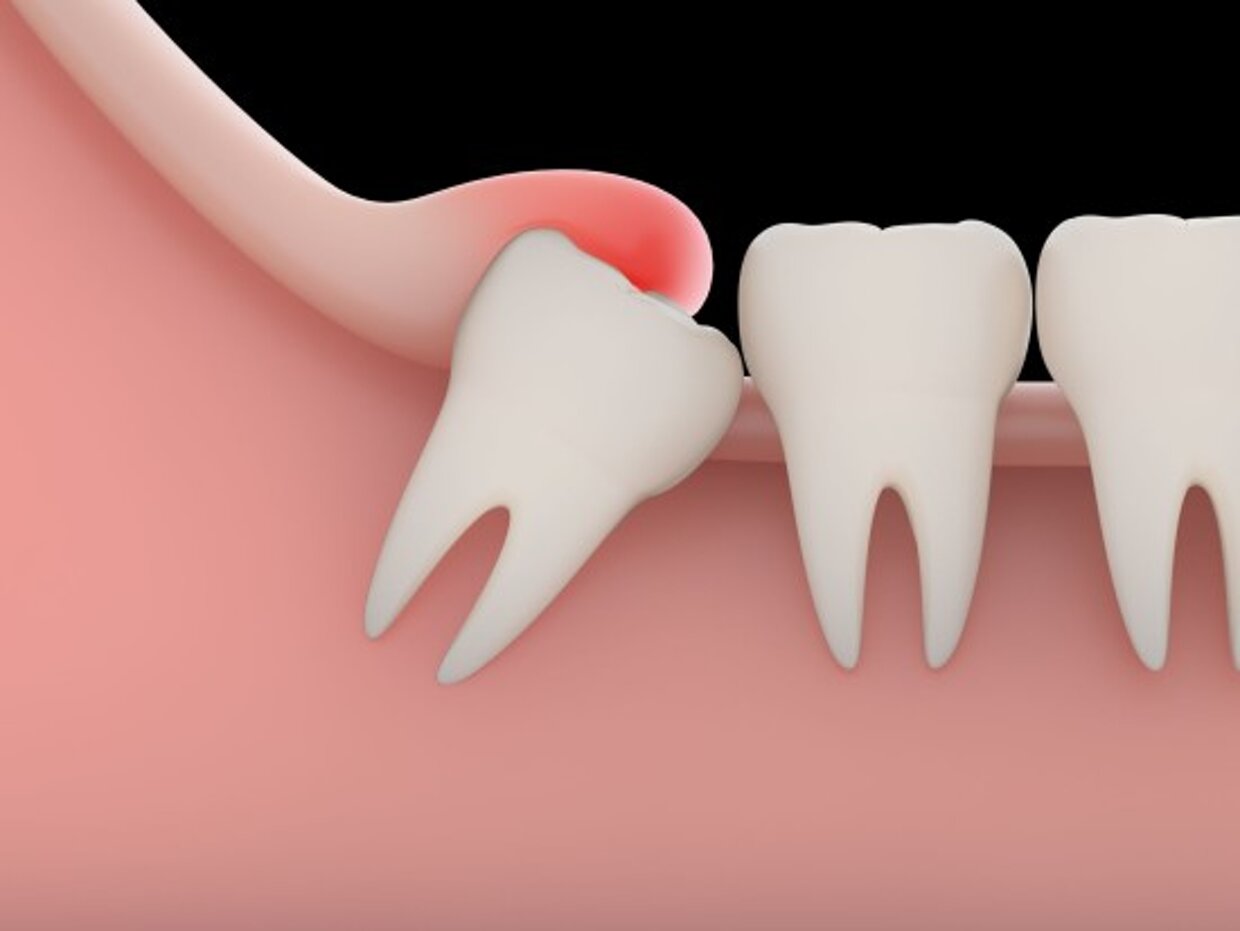

La disodontiasi è un disturbo del fisiologico processo di eruzione degli elementi dentali; si manifesta clinicamente con un tipico quadro infiammatorio. Il dente che più frequentemente va incontro a disodontiasi è il terzo molare e cioè il cosiddetto "dente del giudizio"

Spesso, per via di una mancanza di spazio o un orientamento scorretto durante la fase eruttiva, il dente del giudizio può andare incontro ad inclusione. L'esame radiologico di base è l'ortopantomografia che viene eseguita direttamente in studio e ci consente di capire nell'immediatezza il grado di inclusione dell'elemento dentario, il suo orientamento e i rapporti che contrae con le strutture anatomiche adiacenti. A seconda del caso, può essere necessario ricorrere ad un esame radiologico tridimensionale per avere informazioni ancora più accurate sulla posizione dell'elemento dentario. La terapia della disodontiasi dei denti del giudizio consiste nell'estrazione chirurgica degli elementi dentari.